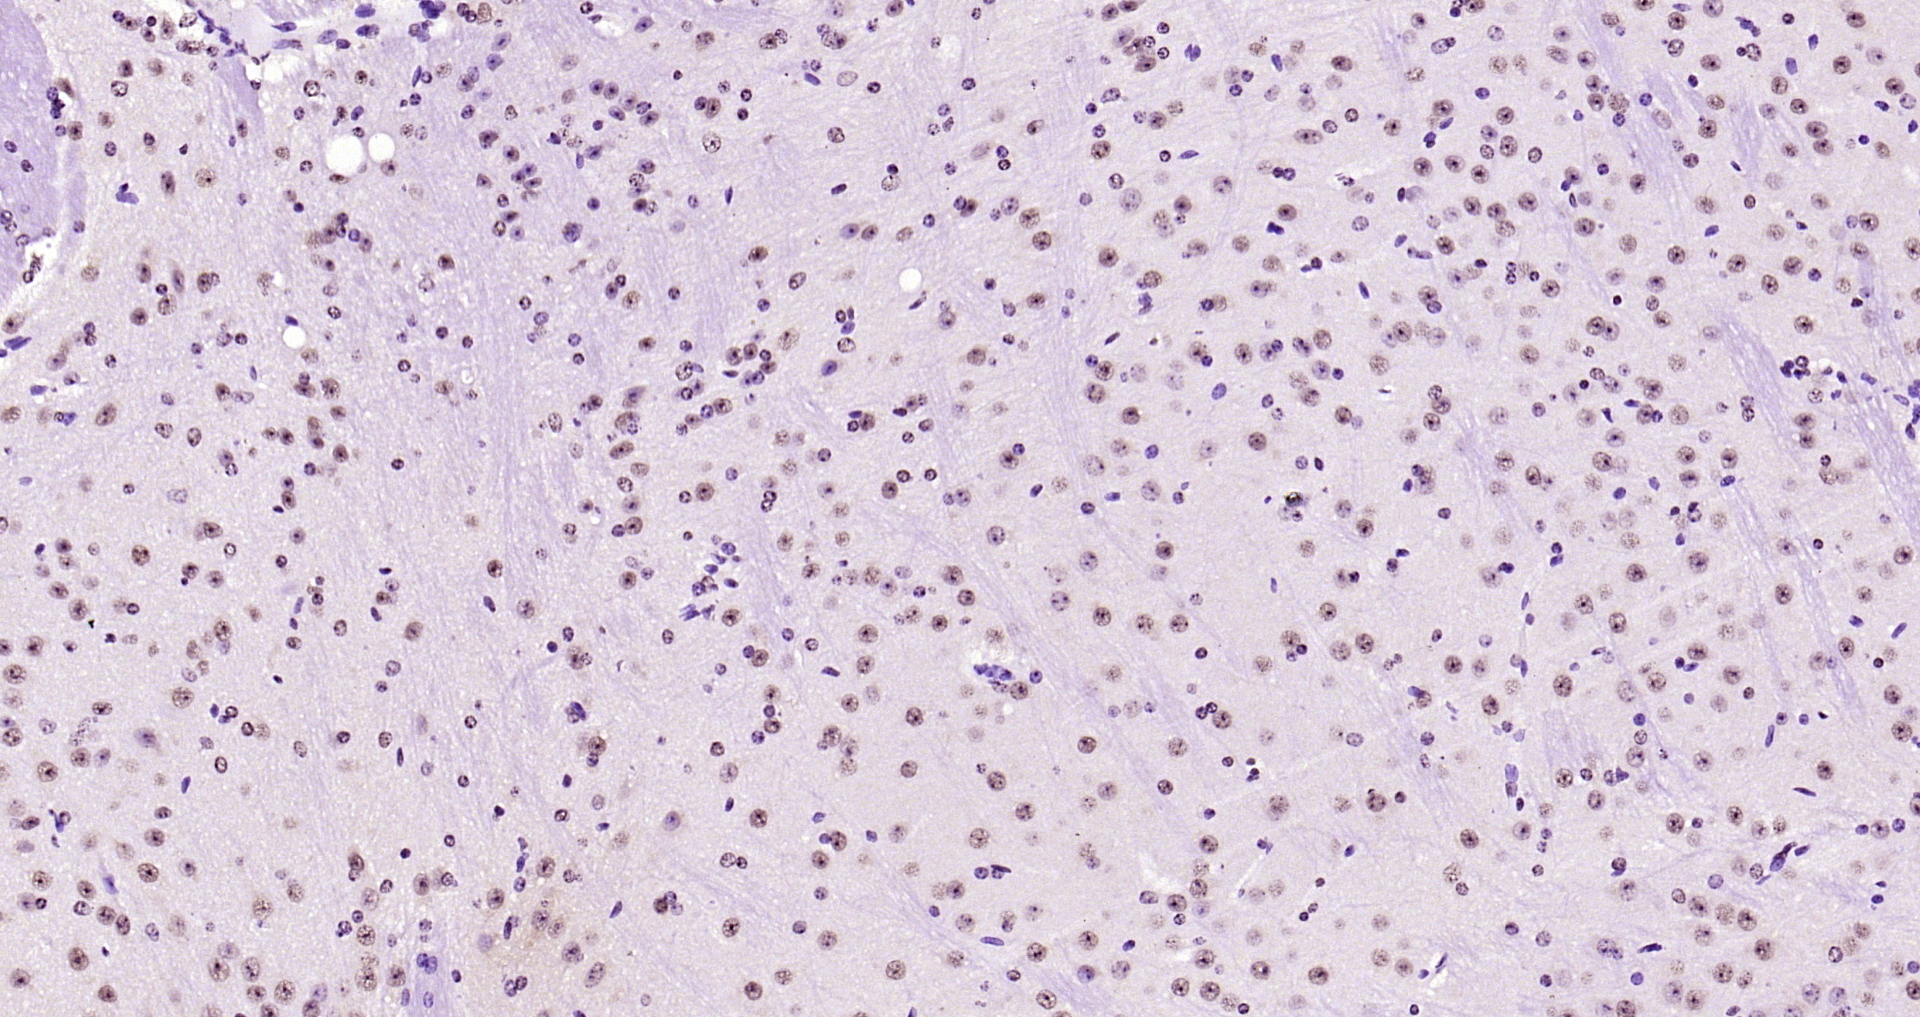

Paraformaldehyde-fixed, paraffin embedded Human colon cancer; Antigen retrieval by boiling in sodium citrate buffer (pH6.0) for 15min; Block endogenous peroxidase by 3% hydrogen peroxide for 20 minutes; Blocking buffer (normal goat serum) at 37°C for 30min; Antibody incubation with SOX9 Polyclonal Antibody, Unconjugated (bs-10725R) at 1:400 overnight at 4°C, DAB staining.